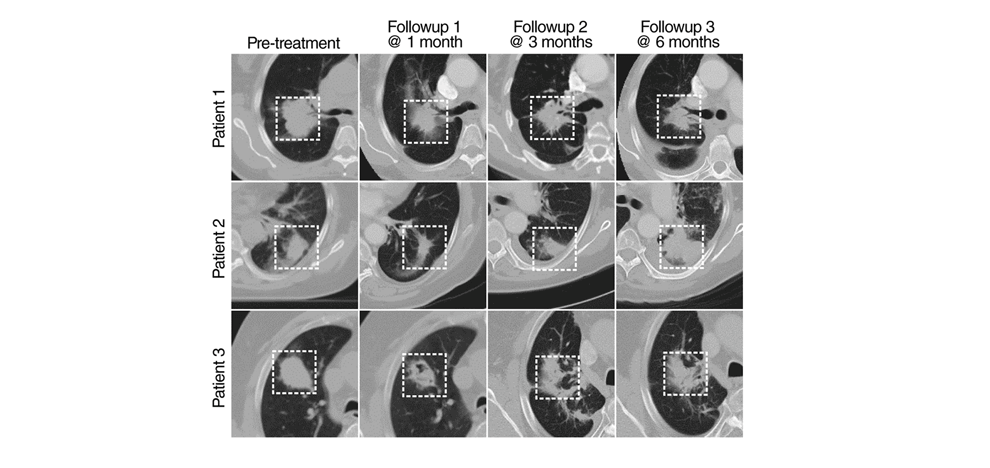

Experimental Design. Dataset A consists of 179 patients with stage III NSCLC treated with definitive chemoradiation, with pretreatment and posttreatment CT images at 1, 3, and 6 months follow-up (581 scans). Models were developed using transfer learning of convolutional neural networks (CNN) with recurrent neural networks (RNN), using single seed-point tumor localization. Pathologic response validation was performed on dataset B, comprising 89 patients with NSCLC treated with chemoradiation and surgery (178 scans).